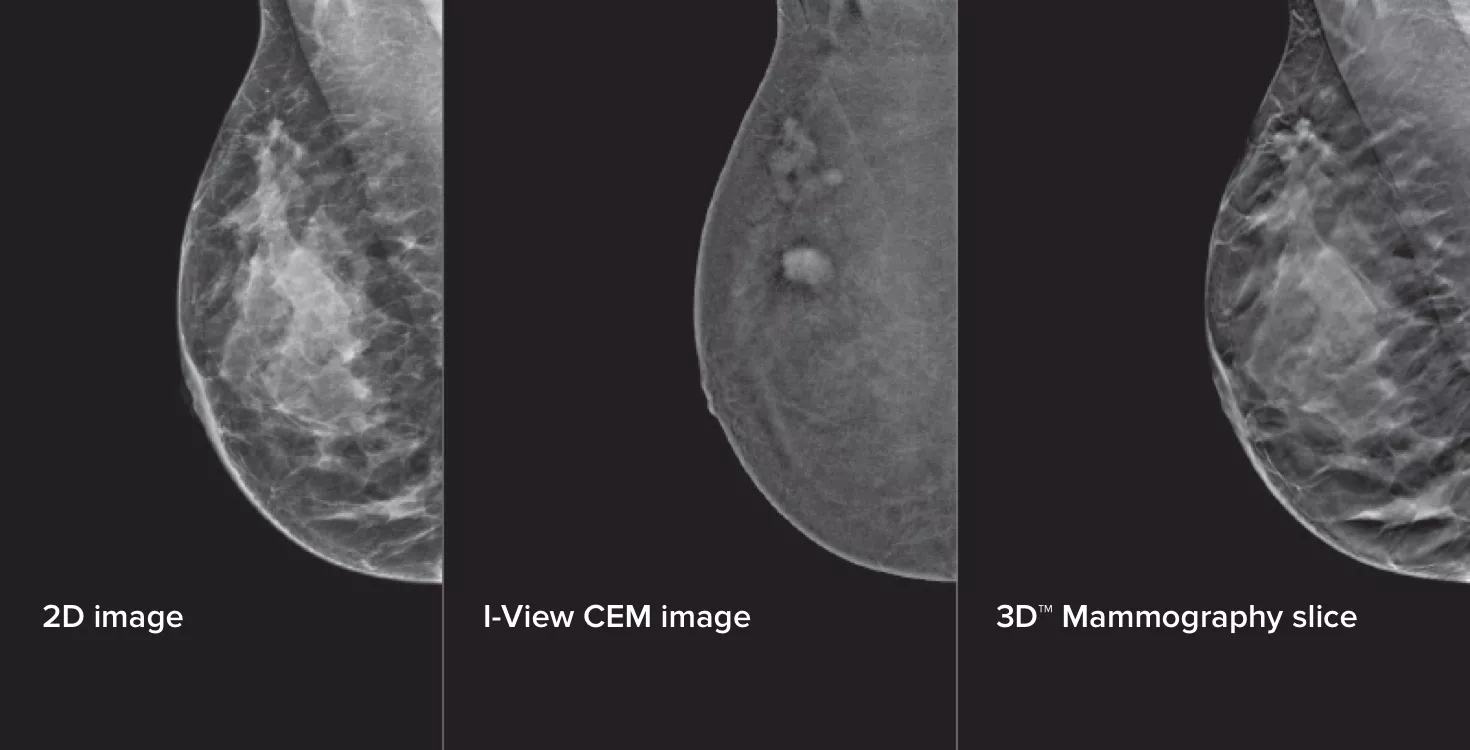

A mamografia com contraste (CEM, do inglês «Contrast Enhanced Mammography»), o sistema de imagem da mama que utiliza contraste de iodo para realçar as áreas com maior fluxo sanguíneo na mama pode ajudar a destacar lesões suspeitas. O software I-View consegue combinar a potência da CEM com as imagens 2D e de tomossíntese, tudo com apenas uma compressão, fornecendo um sistema de imagem anatómico e funcional num único exame.1

Este software captura informações anatómicas e funcionais num único exame, tirando partido da capacidade de fornecer imagens de tomossíntese 2D e com contraste com apenas uma compressão.1